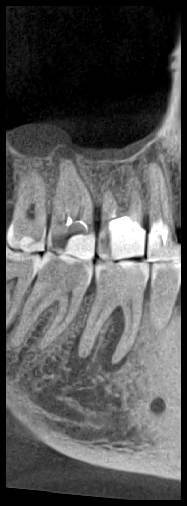

КТ от 28.05.2024

28_05.24(2).jpg.0ffa1febe861106733e1de830afbe6f4.jpg28_05.24-1(2).jpg.9c45d7be16aeed505bd413ce9bc6e69e.jpg28_05.24-2.jpg.a728a7d7e6213c1c8302b43adc89e4d0.jpg28_05.24-4(2).jpg.ac43f3448a3988c7006f74e1d0ce09da.jpg28_05.24-6(2).jpg.dd1fd85c6cc0fcd3d43bd9e71fc0d616.jpg28_05.24-8(2).jpg.885c8cb905445e9308f124fb9e5c616b.jpg28_05.24-9(2).jpg.6cceaaaa1b56d0967482c87b951fbe2d.jpg28.5.24-5(2).jpg.b2d79427a16769c9fd4f0d0911a9db8f.jpg28.5.24-7(2).jpg.f6c17f9820e72dc2708955a65a190b57.jpg28.0524-3(2).jpg.0aa9f153071766a340b428158a94ade8.jpg